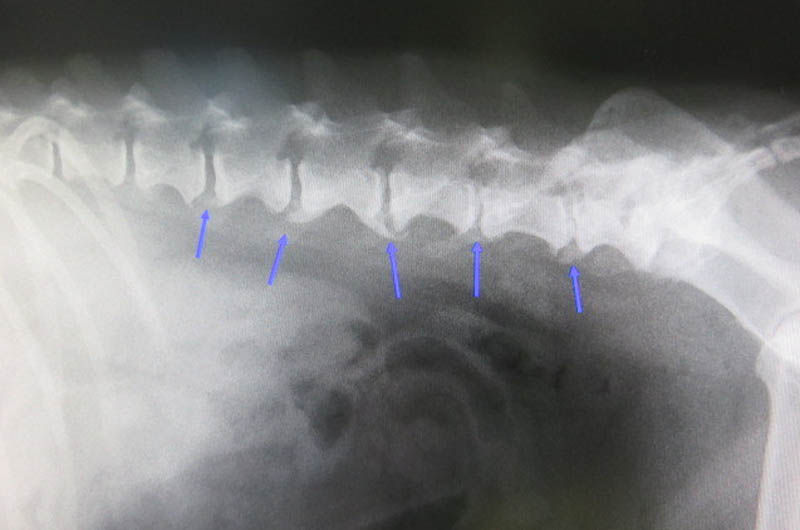

【レントゲン検査】

胸部と腹部を、仰向けの状態と横に寝かせた状態2枚ずつ撮ります。

背骨に異常がありました。

腰椎に変形性脊椎症がでていました。

青矢印の部分に老齢性の骨の変形がでています。

後肢のふらつきや、フローリングで滑りやすくなっているのはこのせいのようです。

思っていた以上に体の老化はすすんでいました。